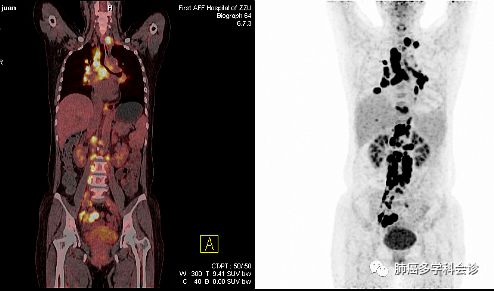

于2017年11月做PET-CT示:右侧附件区软组织肿块代谢活跃,考虑恶性病变;双肺多发结节影部分代谢活跃,胰腺内结节样代谢活跃灶,双侧颈部、纵隔、双肺门、膈上、腹腔、腹膜后及双侧髂血管旁多发肿大淋巴结代谢活跃,考虑转移;右侧胸腔积液,盆腔积液。